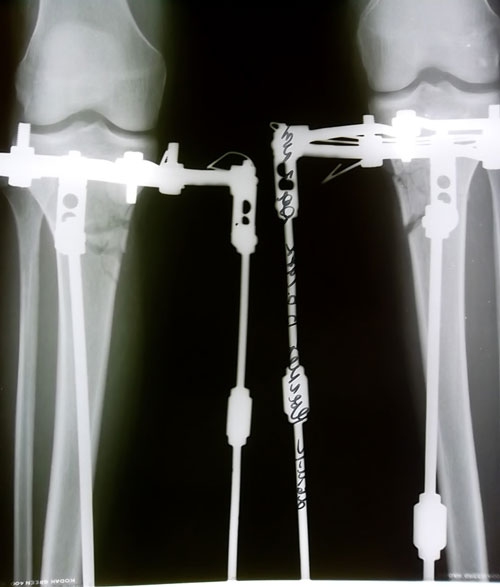

перед крутками.

Вложения

SAM_4383.JPG